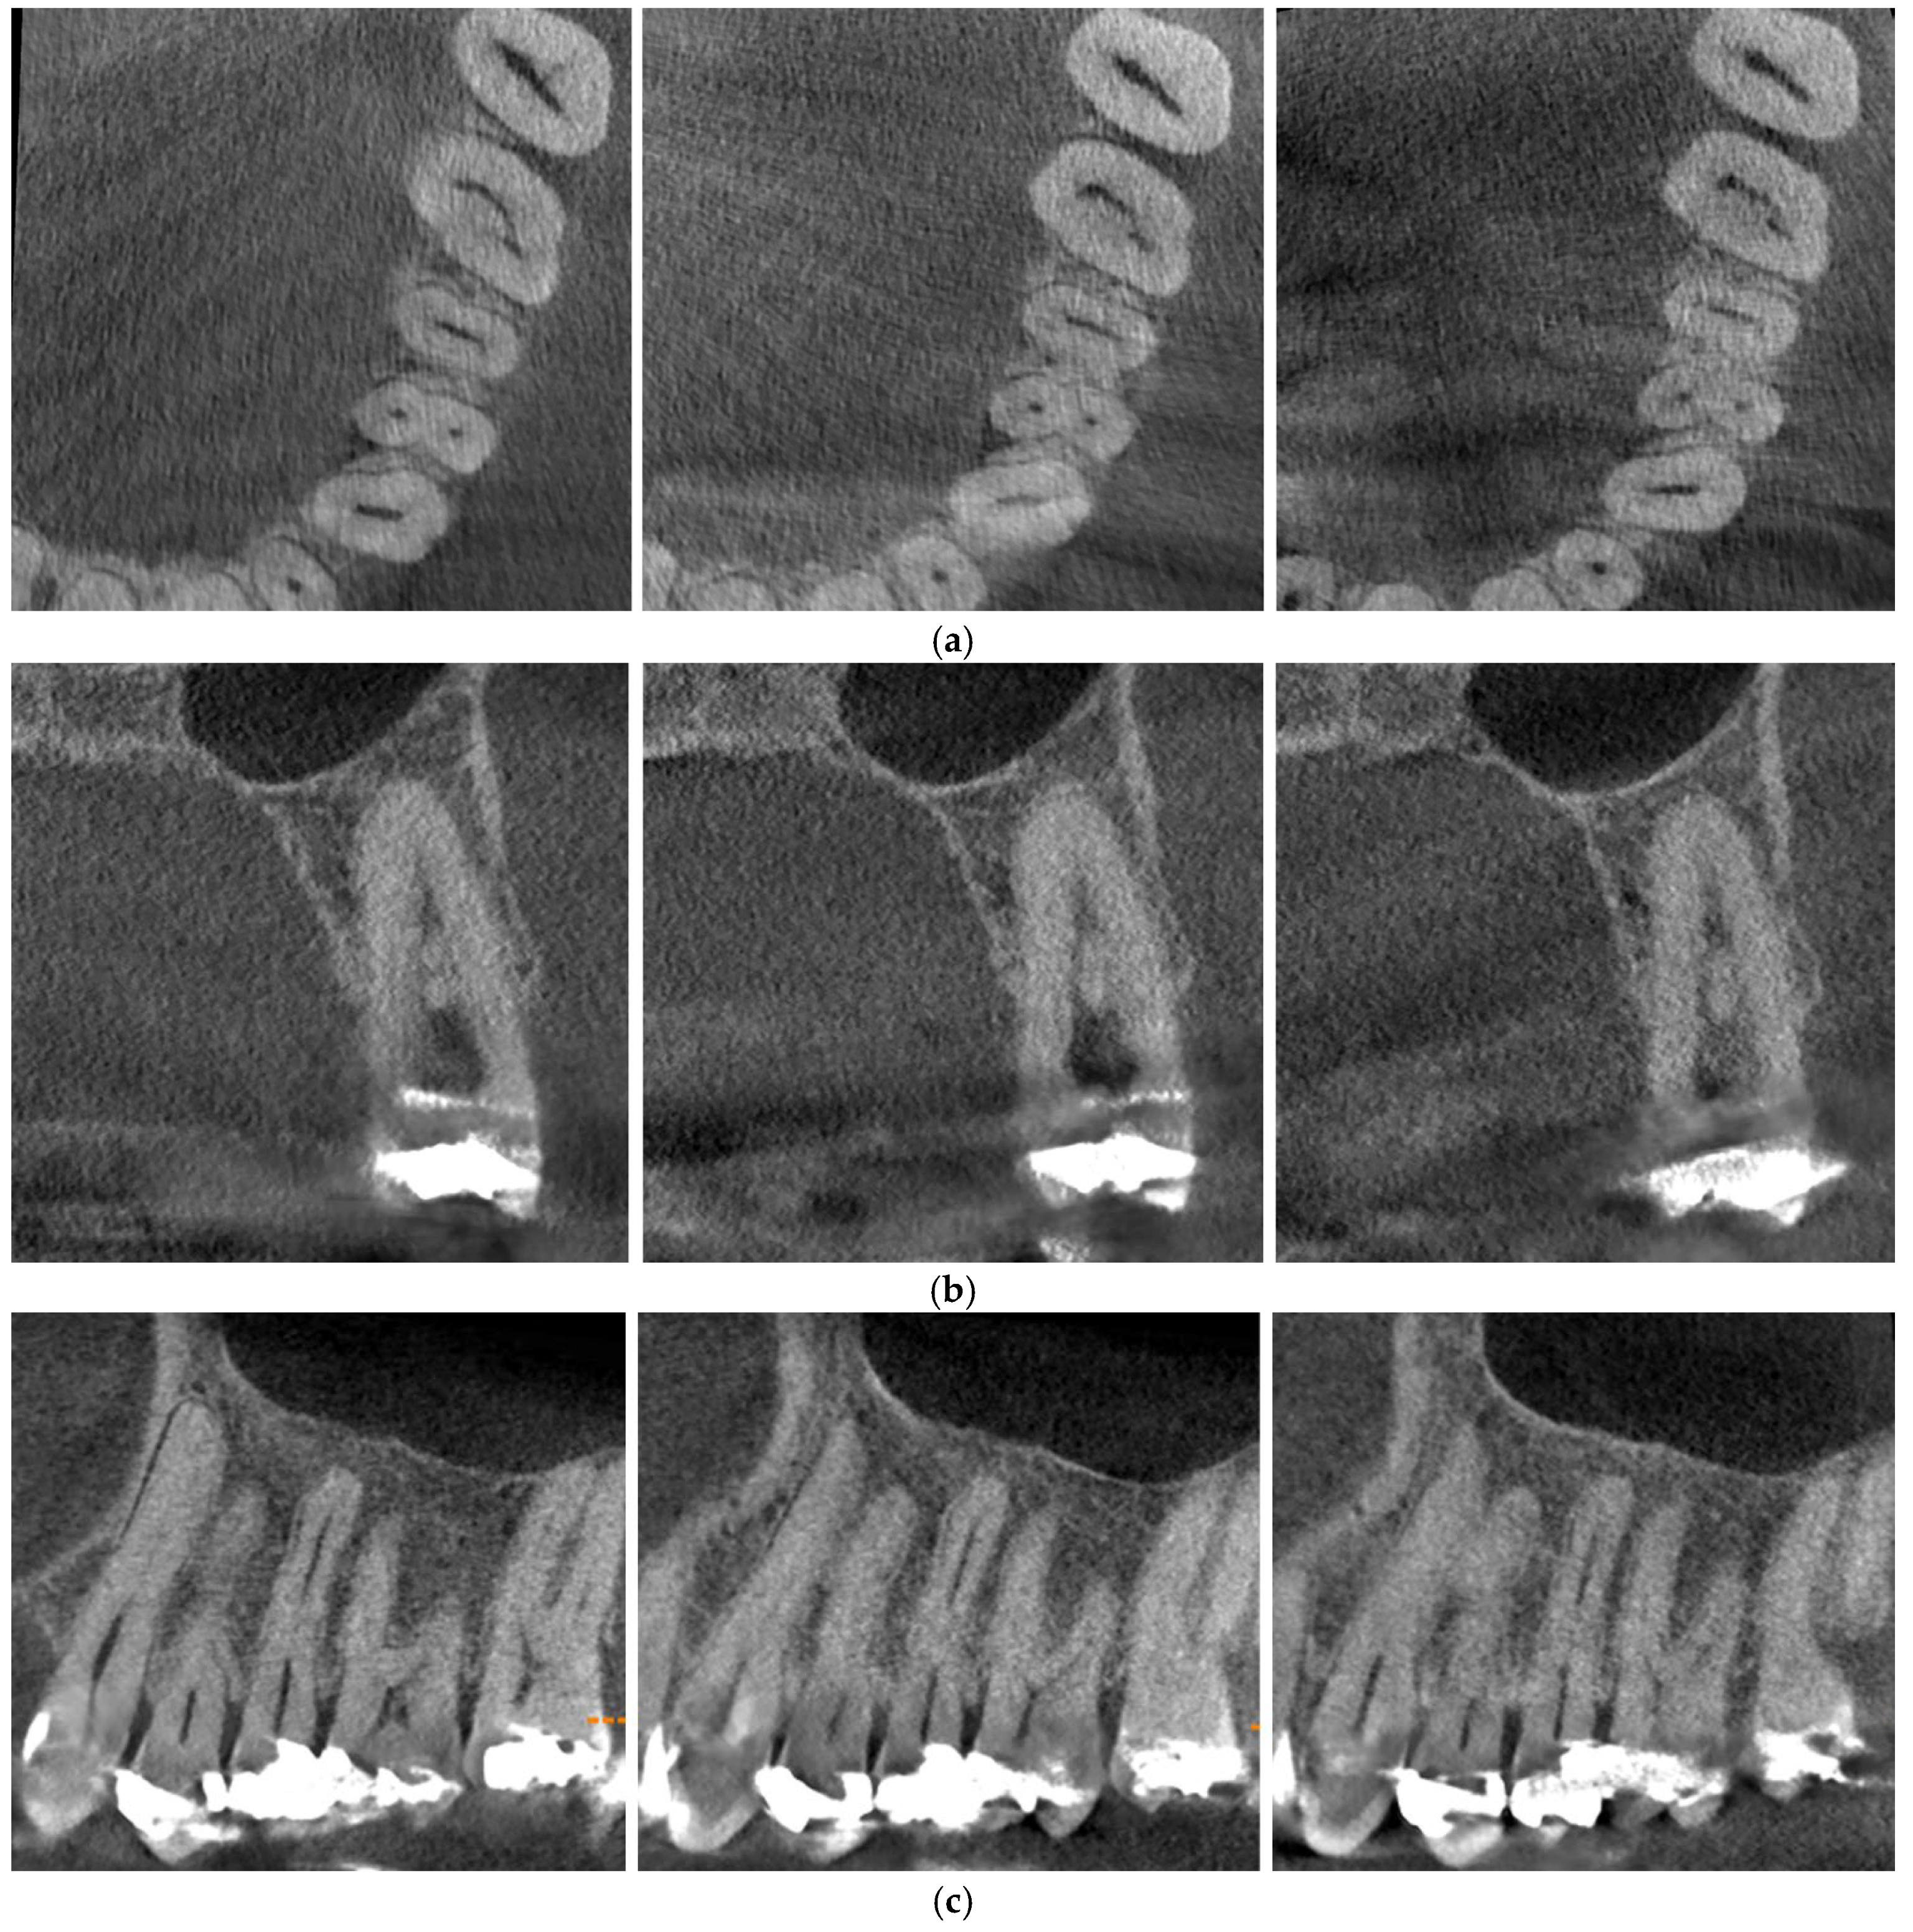

2. Materials and Methods

2.1. Image Acquisition and Experimental Setup

2.2. CBCT Preparation and Image Selection

2.3. Evaluation of Image Quality and Artifacts